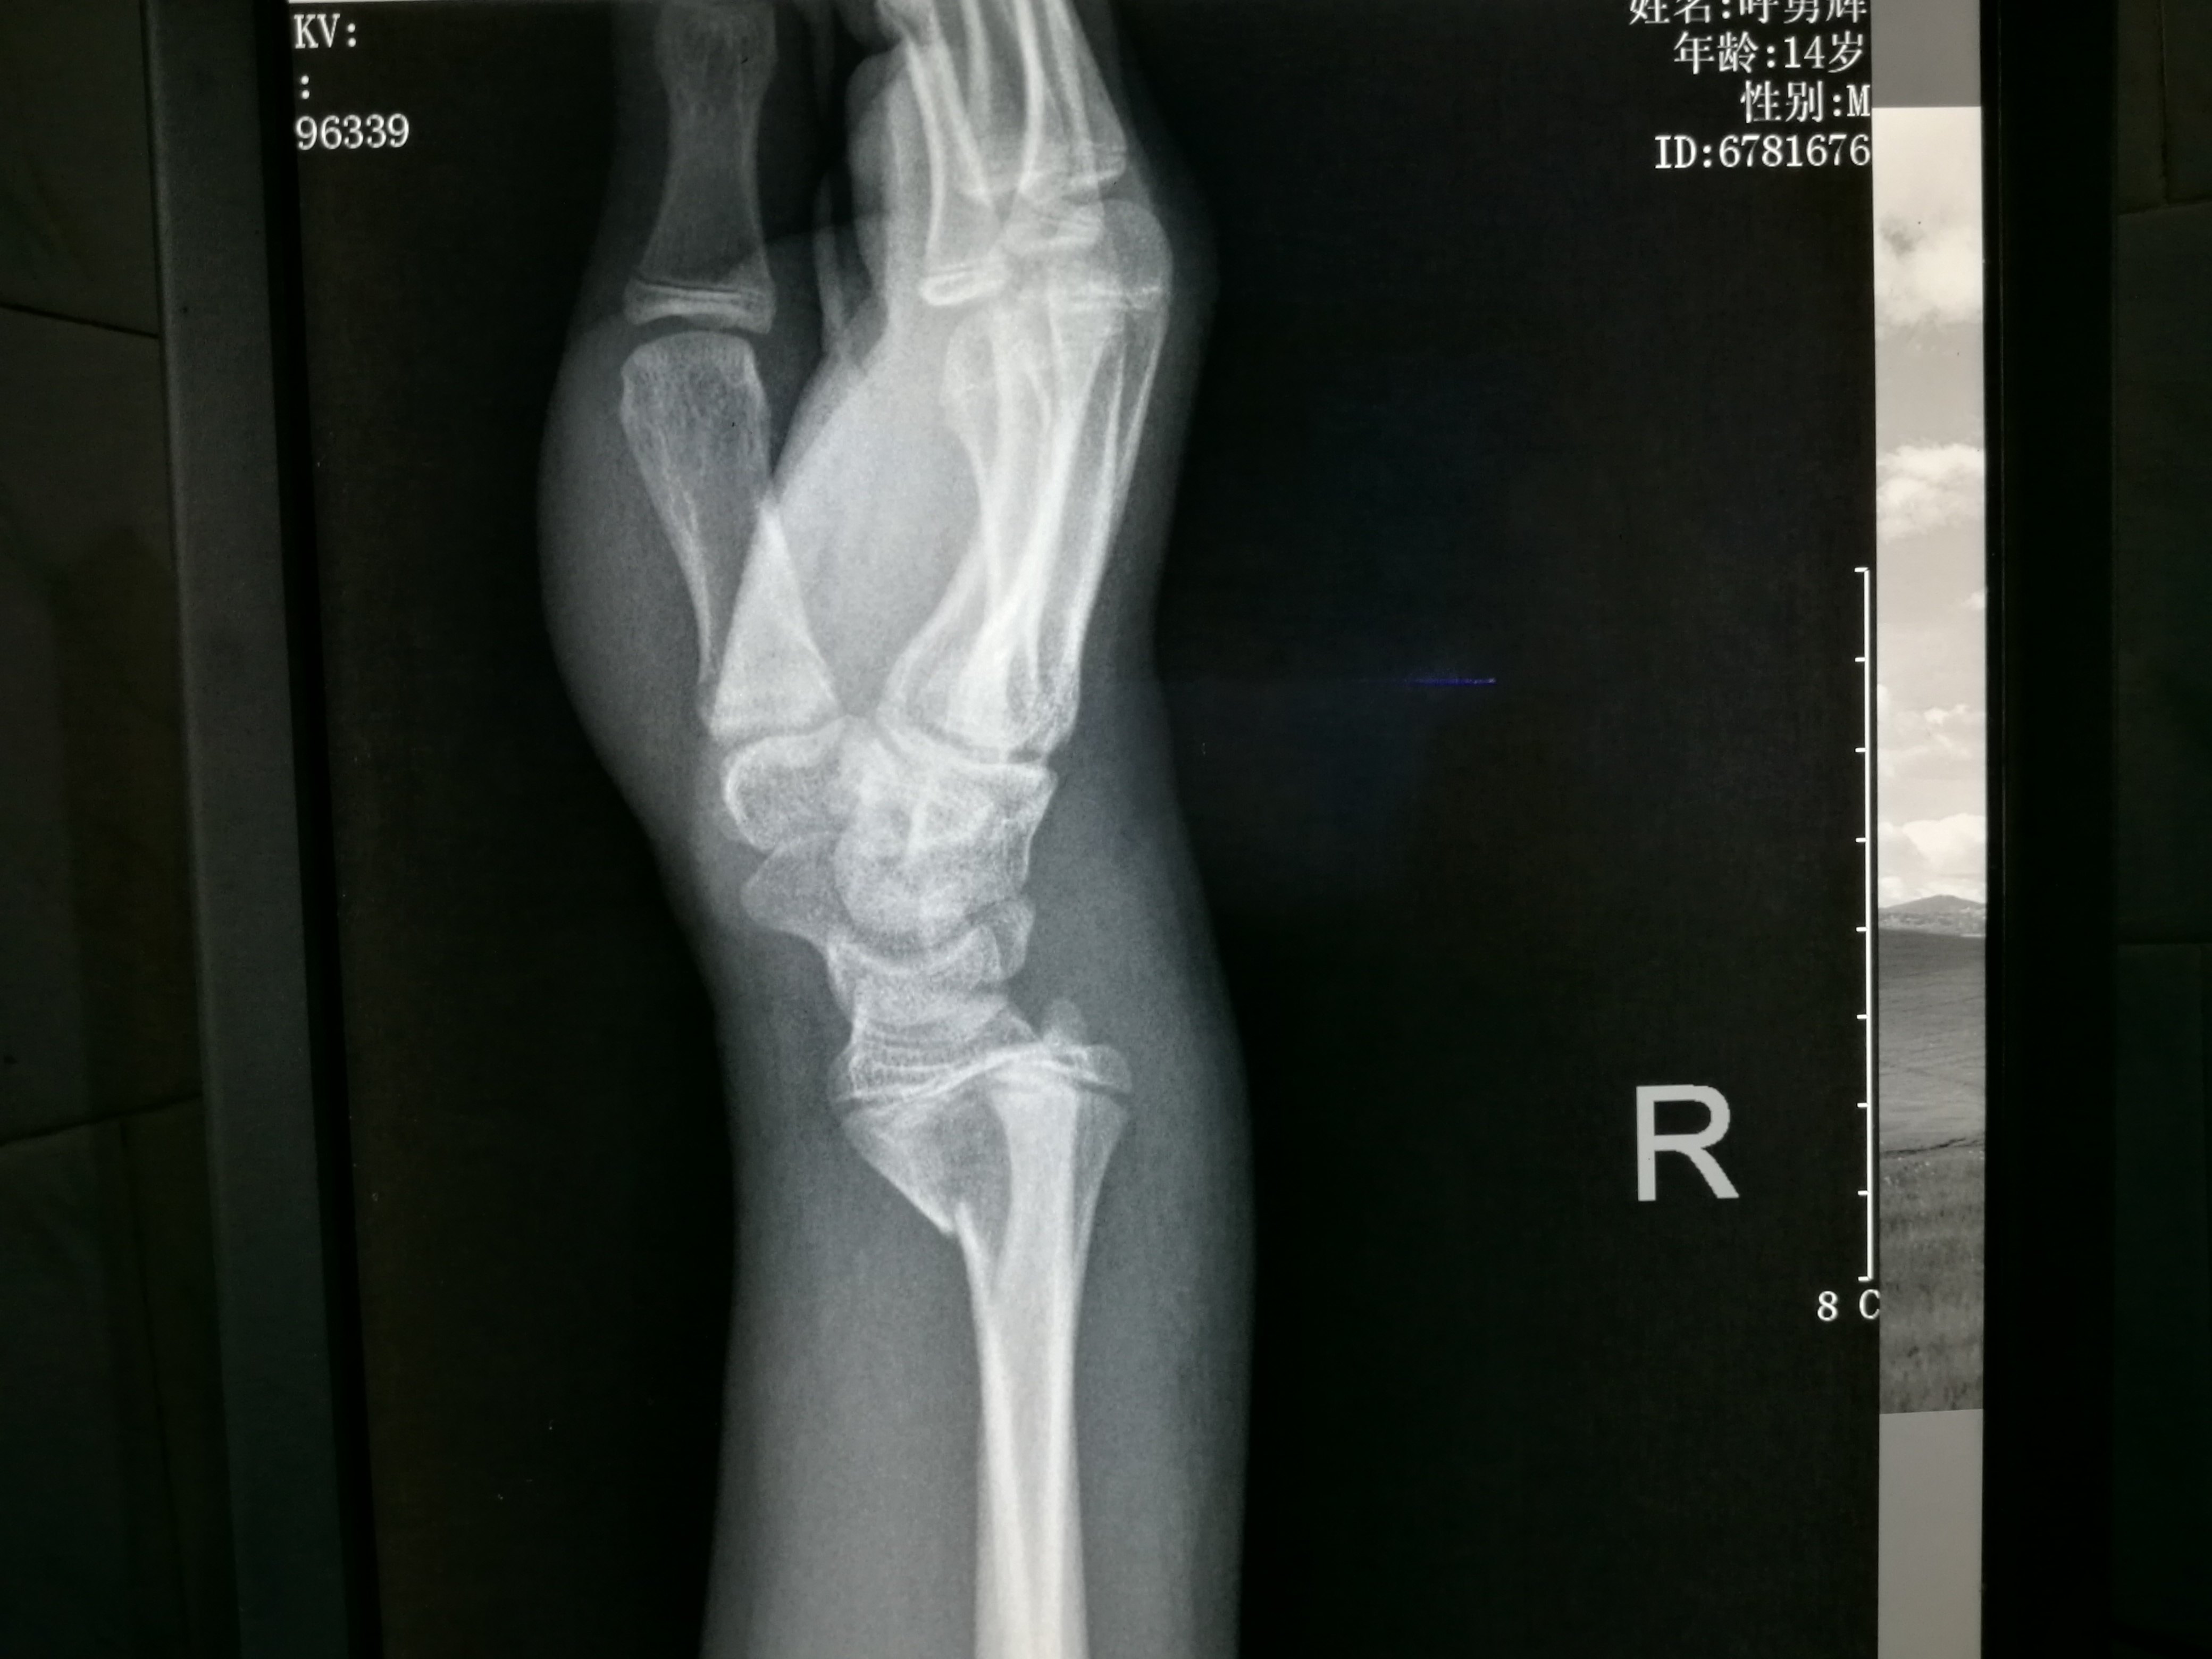

患者 X 男 初步诊断 右手第5掌骨颈骨折 郭氏正骨

患者xx 男 初步诊断 右手第4 5掌骨骨折 郭氏正骨